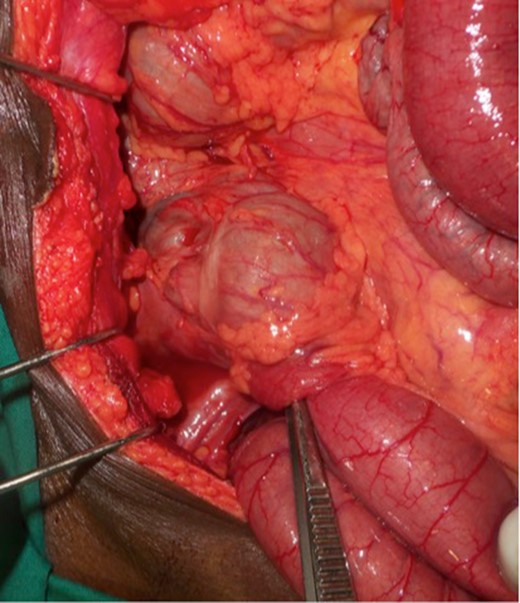

Upon laparotomy, we found an ileocecal intussusception, with mesenteric lymphadenopathies and a dilation of the whole small bowel (Fig. 3). We performed a right hemicolectomy, without attempting to reduce the intussusception, and an end-to-end ileotransverse anastomosis.

The post-operative outcomes were favorable. The pathological examination of the surgical specimen found an adenomatous ileal polyp with a high grade dysplasia on the terminal ileum being the cause of the ileocecal intussusception (Fig. 4).